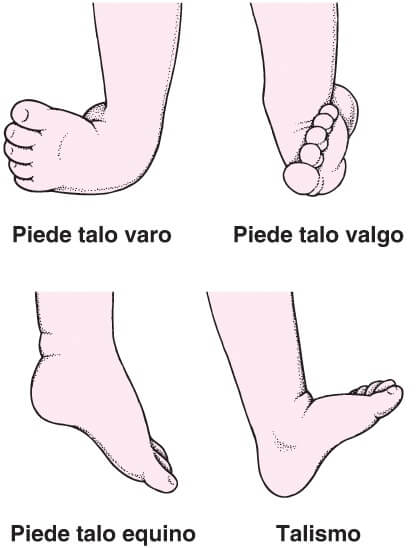

Dismorfismi del piede

Si intendono deformità a carico della struttura Gamba-Piede

Malformazioni Congenite del Piede

Nella grande maggioranza dei casi, le cause sono sconosciute, si può talvolta riconoscere una paralisi o una cattiva posizione del piede durante la vita intra-uterina.